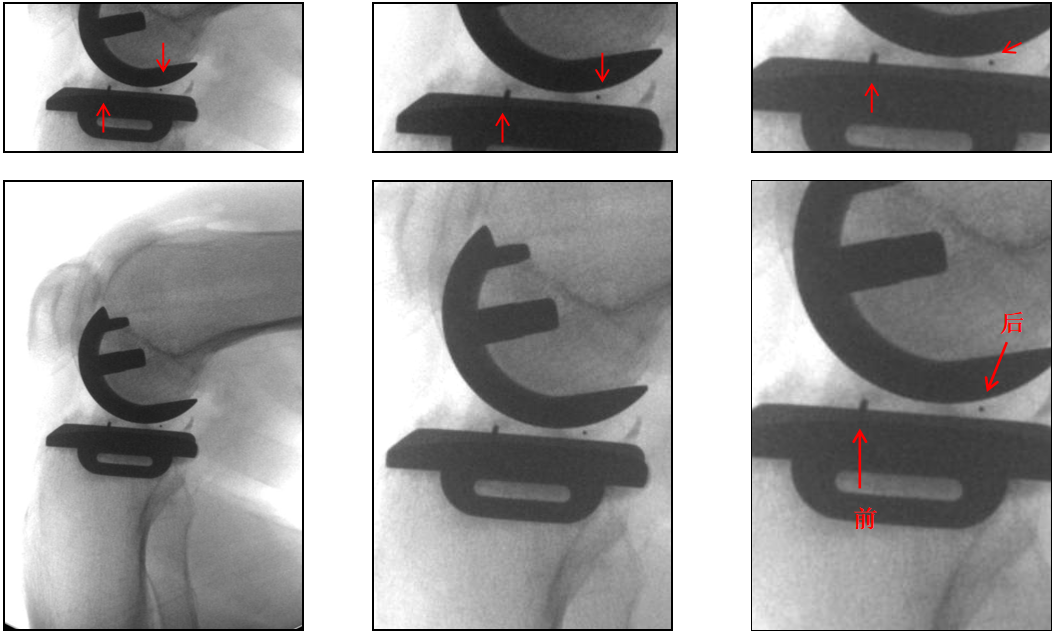

辨认bearing内的标识(透视片正位)

bearing 内的标识:点和线段“ .—. ”线段显示为“—”在前;点显示为“.”在后

辨认bearing内的标识(透视片侧位)

bearing 内的标识:点和线段“ .—. ” 线段显示为“—”在前;点显示为“.”在后

病例展示3

病例3:Bearing 陈旧性前脱位2年

病例3:Bearing 陈旧性前脱位的处理

病例展示4

病例4:内侧OxfordUKA术后6.5年外侧进展性OA

病例4:Bi-UKA术后

病例4:Bi-UKA术后Bearing 后脱位的处理